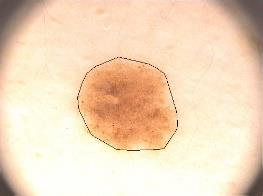

Skin lesion segmentation is one of the crucial steps for an efficient non-invasive computer-aided early diagnosis of melanoma. This paper investigates how color information, besides saliency, can be used to determine the pigmented lesion region automatically. Unlike most existing segmentation methods using only the saliency in order to discriminate against the skin lesion from the surrounding regions, we propose a novel method employing a binarization process coupled with new perceptual criteria, inspired by the human visual perception, related to the properties of saliency and color of the input image data distribution. As a means of refining the accuracy of the proposed method, the segmentation step is preceded by a pre-processing aimed at reducing the computation burden, removing artifacts, and improving contrast. We have assessed the method on two public databases, including 1497 dermoscopic images. We have also compared its performance with classical and recent saliency-based methods designed explicitly for dermoscopic images. The qualitative and quantitative evaluation indicates that the proposed method is promising since it produces an accurate skin lesion segmentation and performs satisfactorily compared to other existing saliency-based segmentation methods.